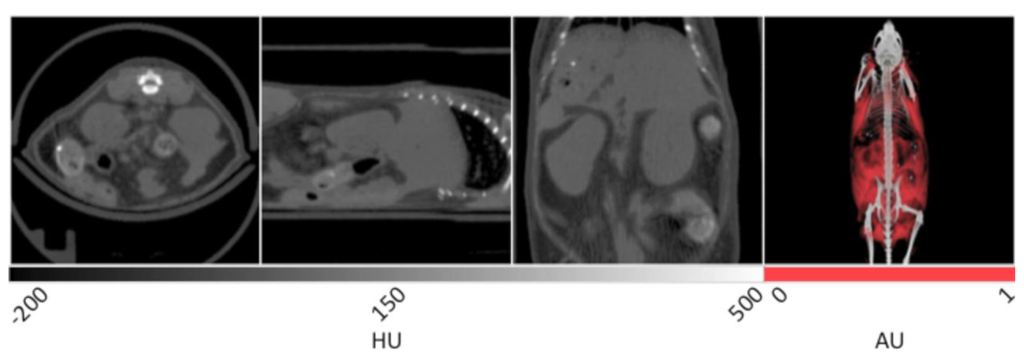

The slice data and a 3D reconstruction of an obese mouse (B6.V-Lep°B/J, male, 12 weeks old) are displayed in Figure 2. In the transverse view shown on the left, significant visceral fat deposits can be observed around the kidneys as lower density volumes owing to the decreased attenuation of adipose. In the sagittal view, more extensive subcutaneous fat deposits can be observed in addition to those in the abdomen. In the coronal view, fat deposits are seen around the kidneys, gastrointestinal tract and liver. The fat volume was segmented in a similar manner as the lungs using PMOD software, however values were bounded to −200 and −50 HU. Once the adipose tissue was segmented and allocated into an independent data set, it was false colored red and overlaid on the original CT to aid visualization. In the right frame of Figure 2, the 3D rendering displays the full extent of the spatial distribution of the fat deposits. Specifically, the extent of the visceral and subcutaneous adipose is highlighted, especially around the limbs and gut area. The segmented adipose tissue may be quantified in units of cm3, and divided by the whole animal volume to give a percent body fat value that may be monitored over time and under different experimental conditions.